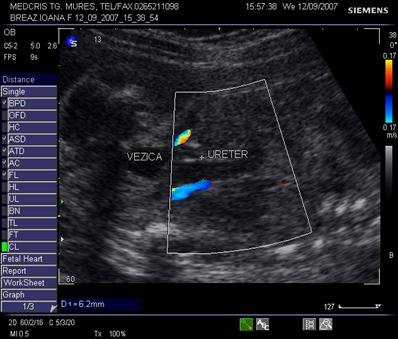

Fig. nr. 276. Megaureter, la 23 sapt la acelasi fat din figurile precedente.